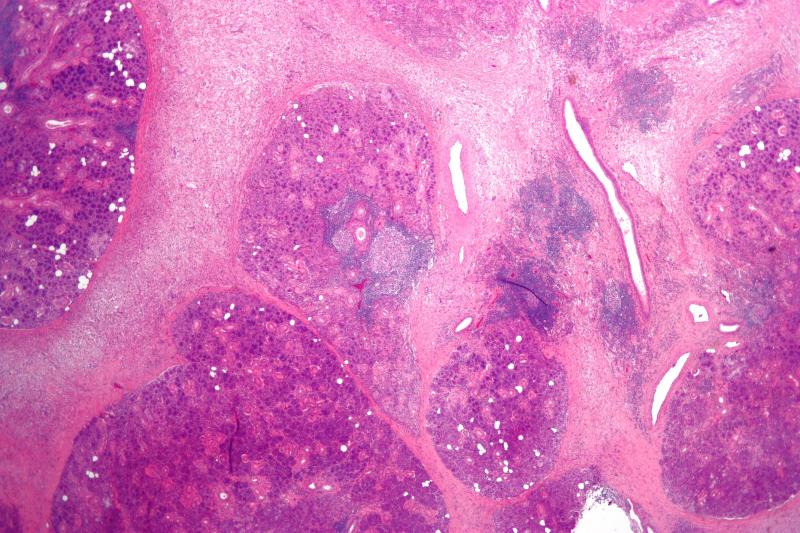

Bacterial Sialadenitis is an infection of the salivary glands caused by bacteria. The market offers various products for the diagnosis and treatment of this condition. These products include antibiotics, pain relievers, saliva stimulants, and surgical interventions. The demand for these products is driven by the rising cases of oral infections and the need for effective treatment options.